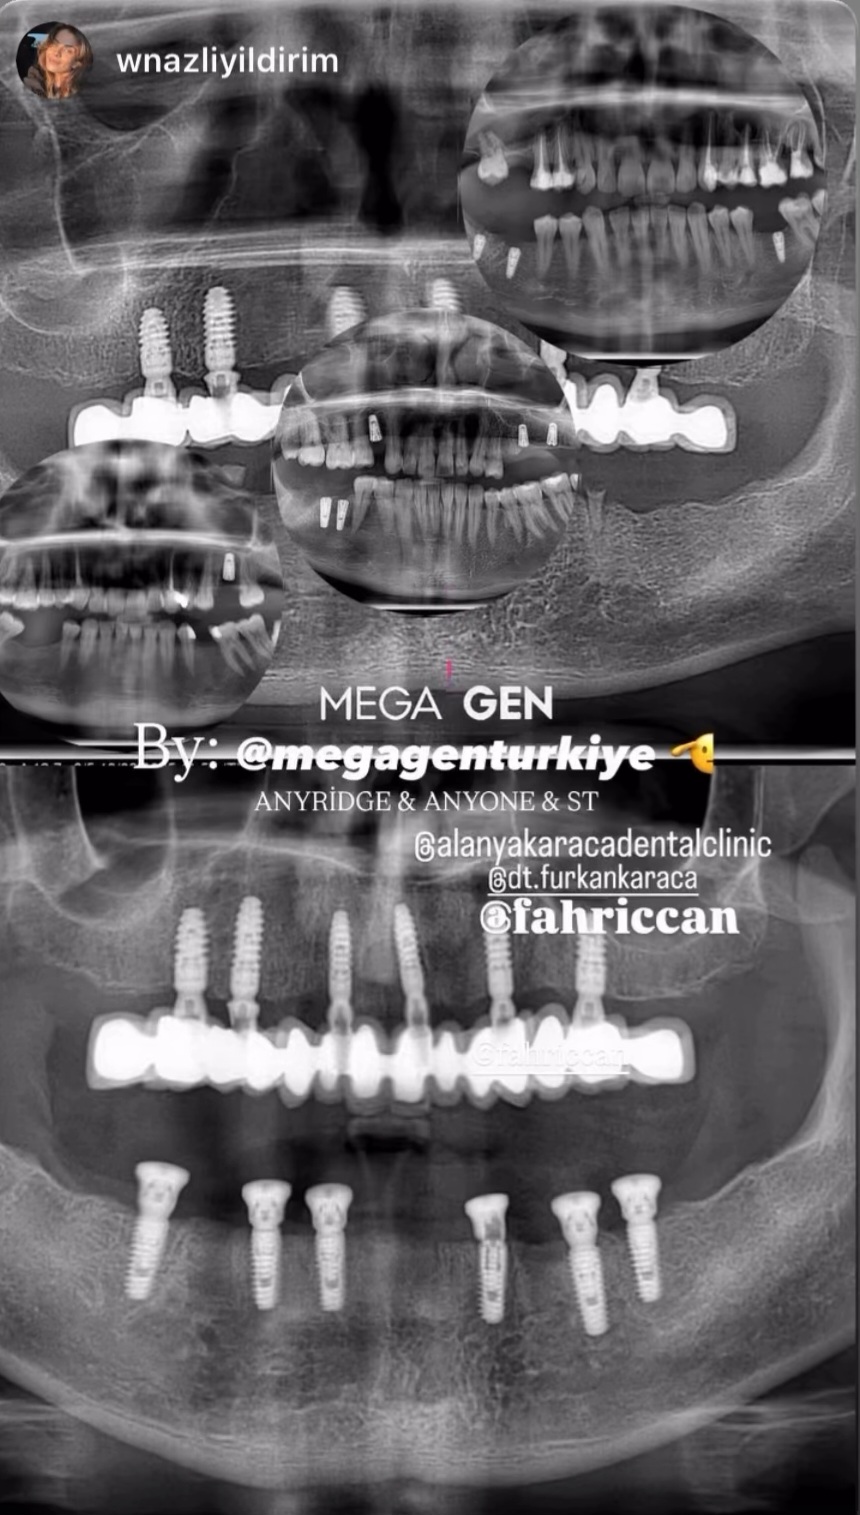

- Diş Dolgusu Kanal Tedavisi İmplant Tedavisi Çocuk Diş Hekimliği (Pedodonti) Lamina Kron Kaplama Zirkonyum Kron Kaplama Estetik Dolgu Estetik Gülüş Tasarımı Hollywood Gülüşü Diş Taşı Temizliği Air Flow Diş Temizleme Diş Beyazlatma Diş Çekimi Gece Plağı Dijital Diş Hekimliği 7/24 Diş Kliniği Hizmeti Acil Diş Kliniği Hizmeti Nöbetçi Diş Kliniği Hizmeti # HİZMETLERİMİZ #